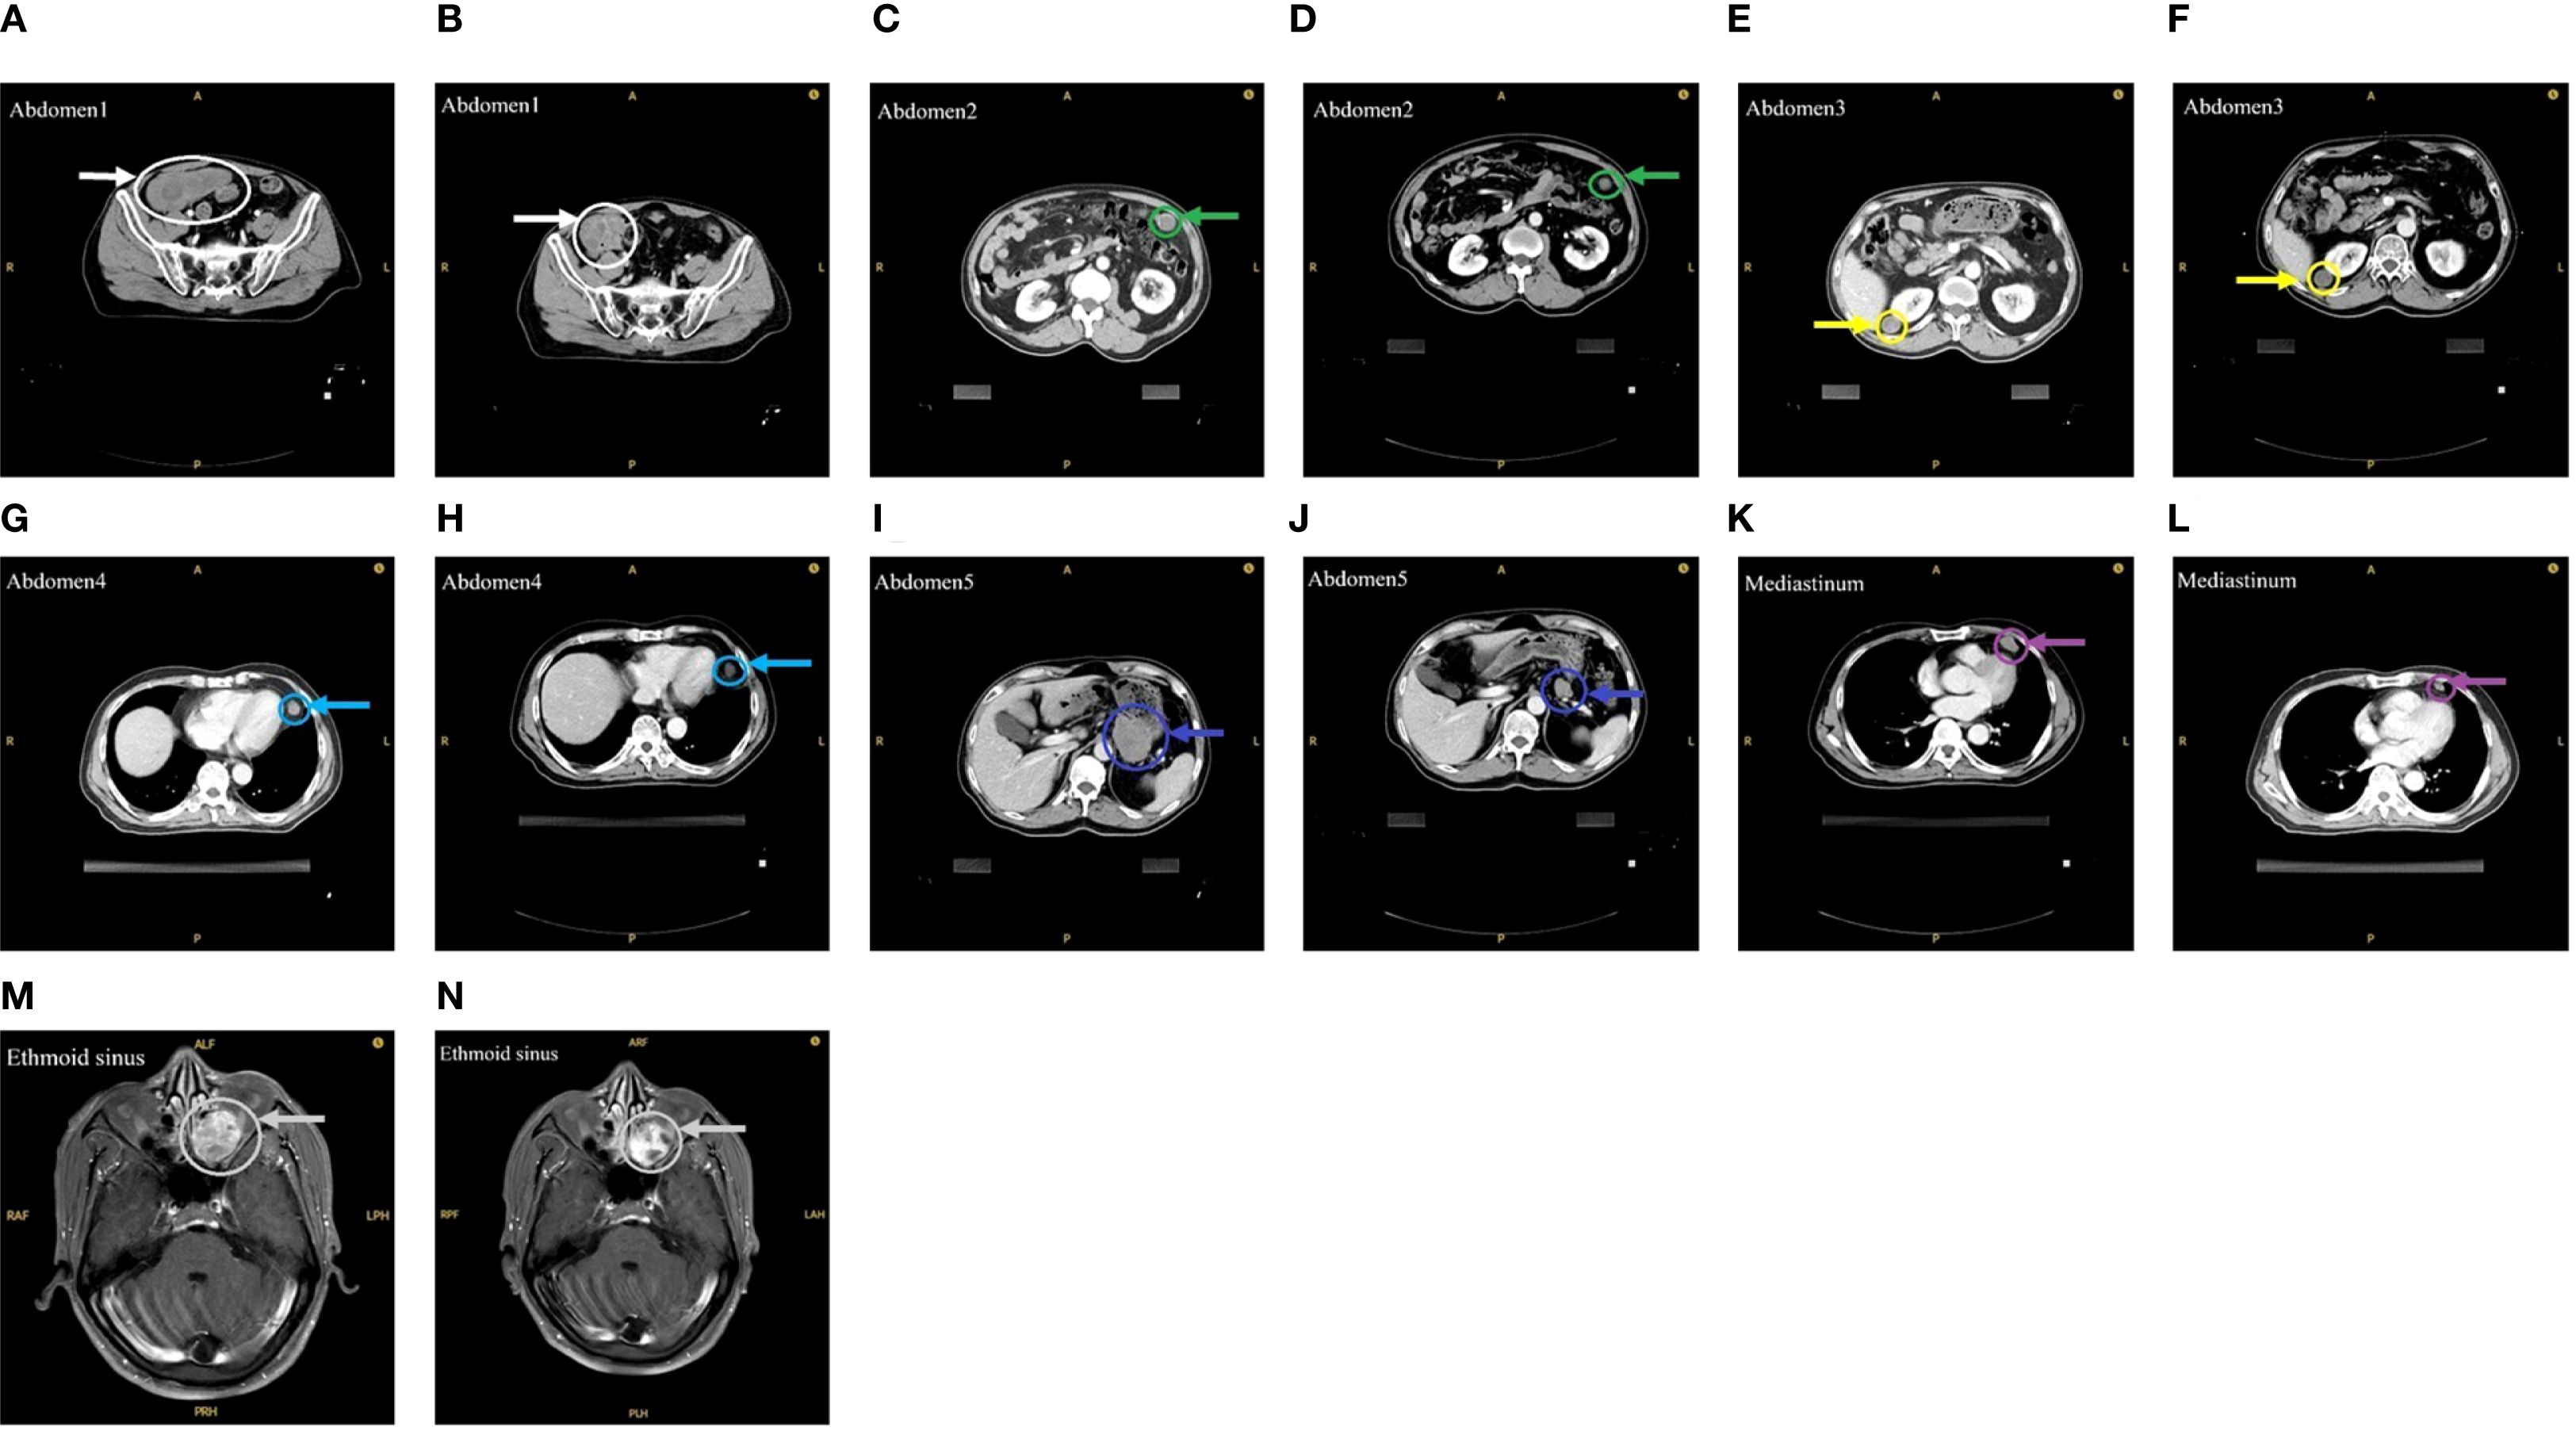

On October 28, 2024, the patient commenced stereotactic body radiation therapy (SBRT), with the largest abdominal lesion receiving a total dose of 25 Gy in 5 fractions (Abdomen1: 25 Gy in 5 fractions). Subsequently, the patient commenced a three-week cycle of combination therapy with toripalimab and apatinib on November 11, 2024. A follow-up CT scan one month later demonstrated PR in the irradiated lesion. (Figures 1A, B). Two weeks later, he received further RT for the remaining larger abdominal lesions (Abdomen2/3/4: 25 Gy in 5 fractions). To minimize gastrointestinal toxicity, a lesion near the stomach was treated with a lower-dose regimen (Abdomen5: 18 Gy in 6 fractions).

Figure 1. Imaging before and after RT. (A) Before the first RT. (B) After the first RT. (C, E, G, I) Before the second RT. (D, F, H, J) After the second RT. (K) Before the third RT. (L) After the third RT. (M) Before the fourth RT. (N) After the fourth RT.

One month after this course of RT, evaluation showed PR in the low-dose field and SD in the high-dose fields (Figures 1C-J). Subsequently, the mediastinal lesions were irradiated (Mediastinum: 18 Gy in 6 fractions). Three weeks later, imaging showed regression of the mediastinal lesions (Figures 1K, L). During this period, the patient developed nasal bleeding, and magnetic resonance imaging (MRI) revealed a metastasis in the ethmoid sinus. The same radiation dose was administered to this site (Ethmoid sinus: 18 Gy in 6 fractions). A follow-up MRI one month later showed regression of the ethmoid sinus lesion in the (Figures 1M, N). After RT, overall tumor burden markedly decreased (Table 2). Among the 7 lesions, 3 achieved PR and 4 showed SD. Notably, the 4 lesions treated with high-dose irradiation exhibited an average reduction of 32.27%, while the 3 lesions receiving low-dose irradiation demonstrated a more pronounced average shrinkage of 66.66%.